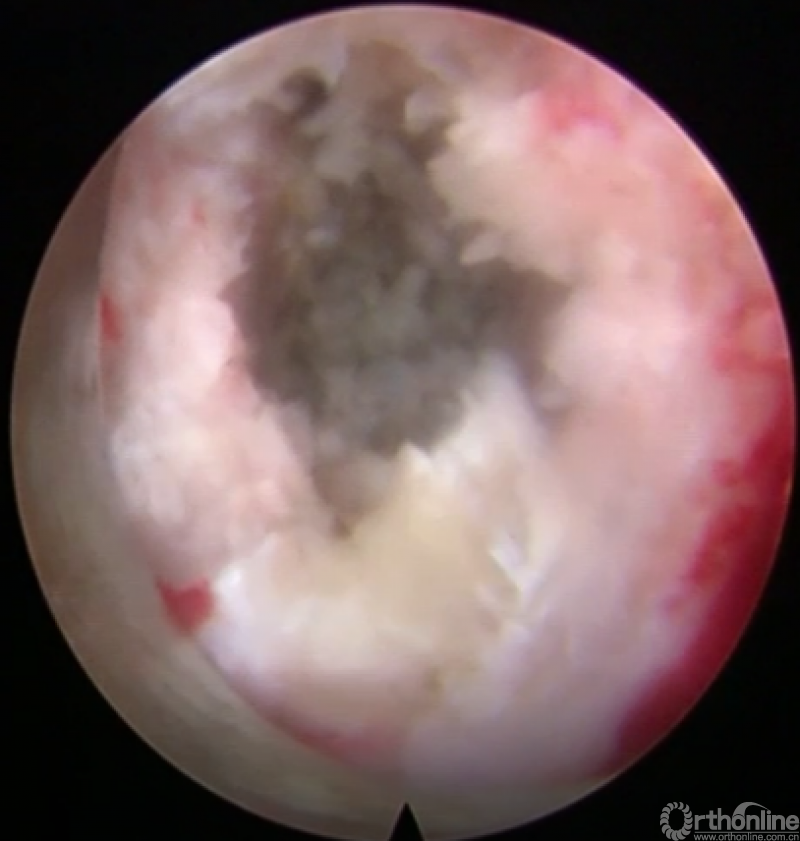

第八步“铰”:盲视下可撑开铰刀置入,撑开并处理上下终板;

第九步“填”;椎间隙填塞植骨;

第十步“置”:置入融合器、经皮钉。